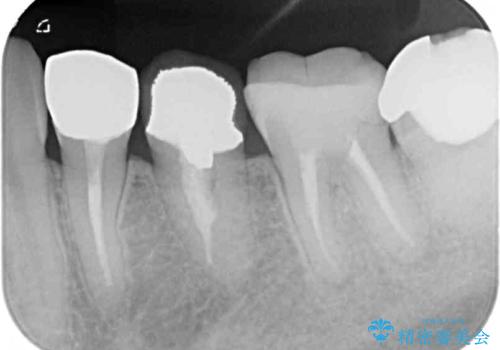

右上の歯は噛んだときに何カ所か痛みを感じるとのことで、診査したところ第二小臼歯が患歯と疑われました。

患者様は他の歯にも痛みを感じるとおっしゃっていましたが、そのような所見が認められなかったため、まずは第二小臼歯を処置し、その痛みが引いた後に再診査することとしました。

右上の歯は、第二小臼歯の初回処置後に痛みを感じなくなったため、他の歯については問題なしと診断しました。